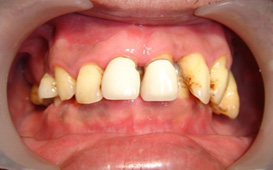

牙周病不處理會怎樣 ?

嚴重時,因為牙齒沒有牙周支撐,將導致牙齒鬆動、脫落。

如果沒有治療,牙齒喪失的數目經常不單只是一顆牙,往往是多顆牙齒,甚至於全口牙拔掉。